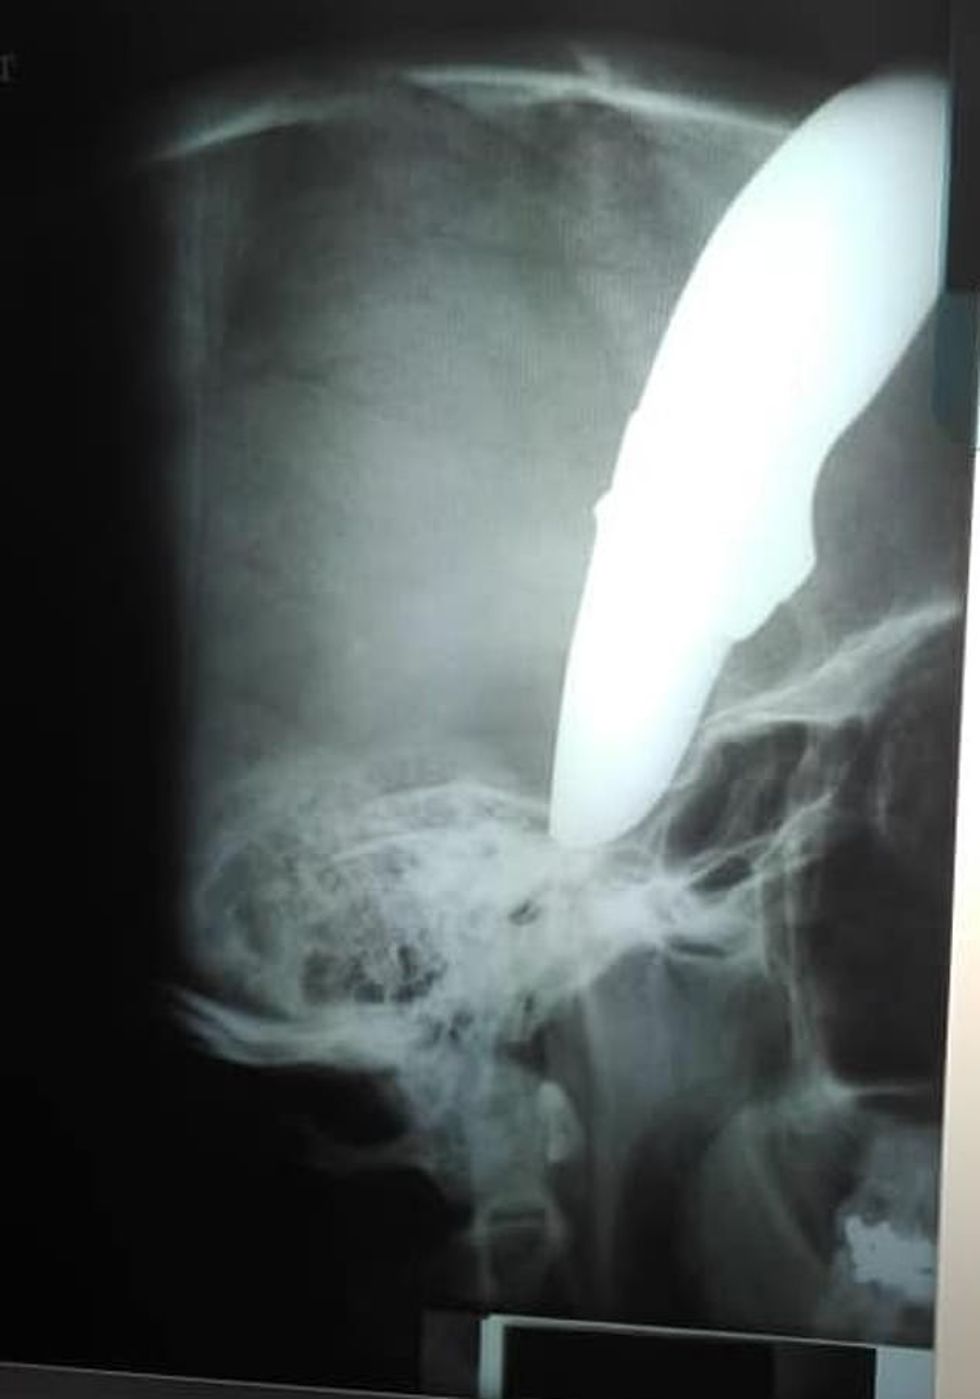

Thika 15 centimetërshe kishte ngecur në kokën e tij derisa sulmuesi po mundohej t'ia vidhte biçikletën, dhe është interesant se si përkundër plagës së marrë kishte arritur t'i rrah të dy sulmuesit.

Sikur kjo të mos mjaftonte, ai hipi në biçikletë dhe u nis për në spital për t'ia hequr thikën e ngulur në kokë. Mjeku Brendan Venter, 48-vjeç, ka deklaruar se si kolegët e kishin informuar se një pacient me thikë në kokë po e priste në korridor.

"Ai ishte shumë i sjellshëm dhe për asnjë moment nuk bëri panik. Për fat të mirë thika në kokë nuk kishte prekur pjesët vitale që mund ta mbysin", ka shtuar mjeku Venter. /Telegrafi/